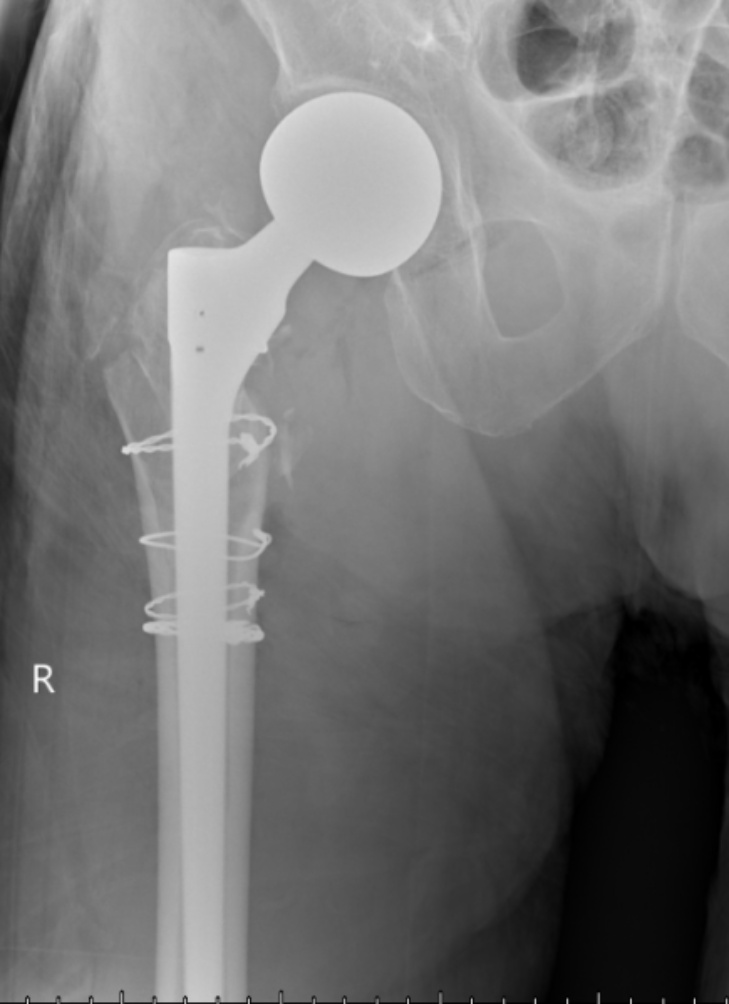

典型病例影像学表现见图1~10。图1为86岁女性右侧股骨转子间骨折(Evans Ⅲ型)患者,术前X线示骨折断端部分错位,术后X线示骨折位置可以及假体位置良好;图2显示了一名81岁男性患者,诊断为左侧股骨转子间骨折,类型为Evans V型,合并股骨干陈旧性骨折。患者接受了生物型加长柄半髋关节置换手术,并进行了股骨近端的钢丝捆扎内固定。术后X线示假体位置良好,股骨近端予钢丝捆扎固定;图3为87岁女性左侧股骨转子间骨折(Evans V型)患者,术后X线示假体位置良好,股骨大小转子骨折位置可,钢丝捆扎固定在位有效;图4为75岁女性左侧股骨转子间骨折(Evans V型)患者,术前X线示左侧股骨转子间骨折PFNA术后、骨折未愈合、内固定断裂。术后假体匹配良好,股骨近端钢丝内固定稳定可靠;图5为75岁男性左侧股骨转子间骨折(Evans IV型)患者,术后股骨大转子出现轻度位移,假体位置正常。图6为87岁男性左侧股骨转子间骨折(Evans V型)患者,给予DAA入路加长柄半髋关节置换,术前X线片,清晰地显示出左侧股骨转子间的骨折情况,术后X线影像,显示股骨的大小转子骨折位置良好,钢丝内固定装置在位稳定,假体位置良好;图7为77岁女性右侧股骨转子间骨折(Evans V型)患者,术前X线片显示右侧股骨转子间存在骨折且股骨大小转子均有累及和移位,术后X线片显示股骨小转子轻度移位,内固定装置位置稳定,假体位置良好;图8为70岁男性左侧股骨转子间骨折(Evans III型)患者,术前的X线片,清晰地显示了左侧股骨转子间的骨折情况,股骨近端髓腔钙化灶,术后假体位置满意;图9为77岁女性右侧股骨转子间骨折(Evans V型)患者,术前X线片,显示右侧股骨转子间及转子下部位骨折情况。术后假体匹配良好;图10为71岁男性右侧股骨颈骨折(Evans IV型)患者,术前X线片,显示右股骨转子间骨折的情况;术后X线表明股骨的大转子和小转子骨折位置保持良好,内固定装置稳固,术后假体位置正常。

(a) (b)

Figure 4. A 75-year-old female patient with left intertrochanteric fracture of the femur (Evans V type). (a) Before surgery; (b) After surgery

4. 75岁女性左侧股骨转子间骨折(Evans V型)患者。(a) 术前;(b) 术后